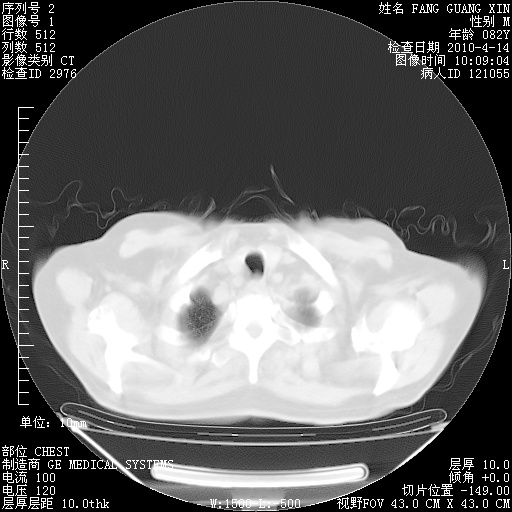

4月14日肺部CT

楼主| 发表于 2010-4-28 16:49 | 显示全部楼层

2.JPG

3.JPG

4.JPG

5.JPG